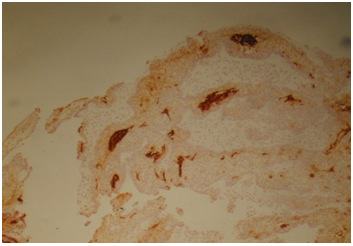

HMW cytokeratin was positive in all 22cases in all squamous parts (Figure 4). Cytokeratin 19 was positive in PBC and SR but negative in SMS and WK parts (Figure 5). Cytokeratin 20 was negative in all squamous parts. LMW cytokeratin: was positive in the PBCs and SMS but reduced in SR and negative in WK in 17/22cases (Figure 6). Cytokeratin 7 was positive in the SR but not in the PBC, SMS or WK in 19/22cases (Figure 7). Cytokeraitn 5/6 was positive in all three layers SMS, SR and PBC but negative in wet keratin in 22/22 cases (Figure 8).EMA was positive in SR and WK, but negative in PBC and SMS in 17/22cases (Figure 9).p63 was positive in PBC and SR cells, but negative in WK and SMS in 16/22cases (Figure 10).p16 was positive in PBC and SR in 15/22cases (Figure 11).Twelve cases show positive p53 immunostainings with range 2%-50% of the cells (Figure 12). Ki67 showed more than 10% positivity in 13cases (Figure 13) and low positivity or negative in 12cases. B-catenin was positive in PBC in 11cases in cytoplasmic and nuclear pattern and was positive in 11cases in cytoplasmic pattern only.

Figure 4 HMWC was positive in all 22 cases in all squamous parts.